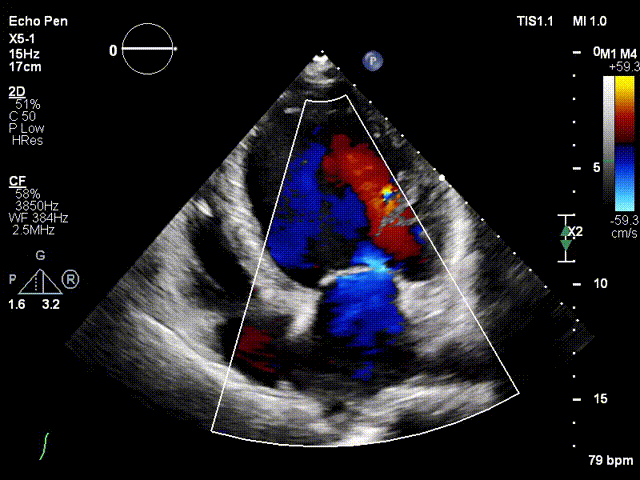

术前二尖瓣反流

术后无反流